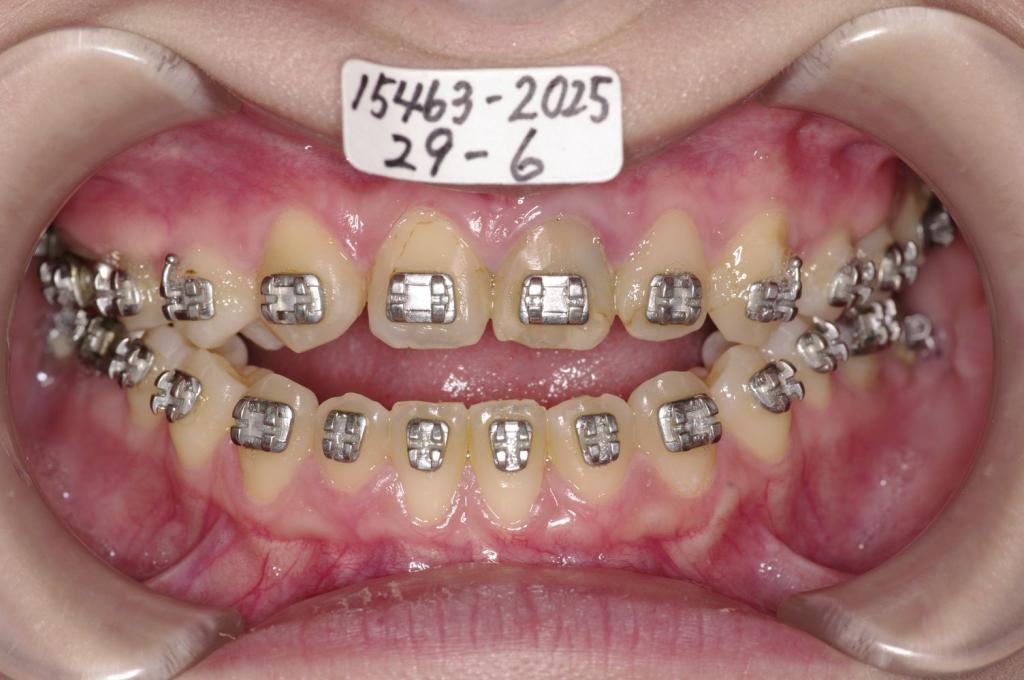

- 顎、顔の歪みの矯正治療

- 受け口 顎の歪み